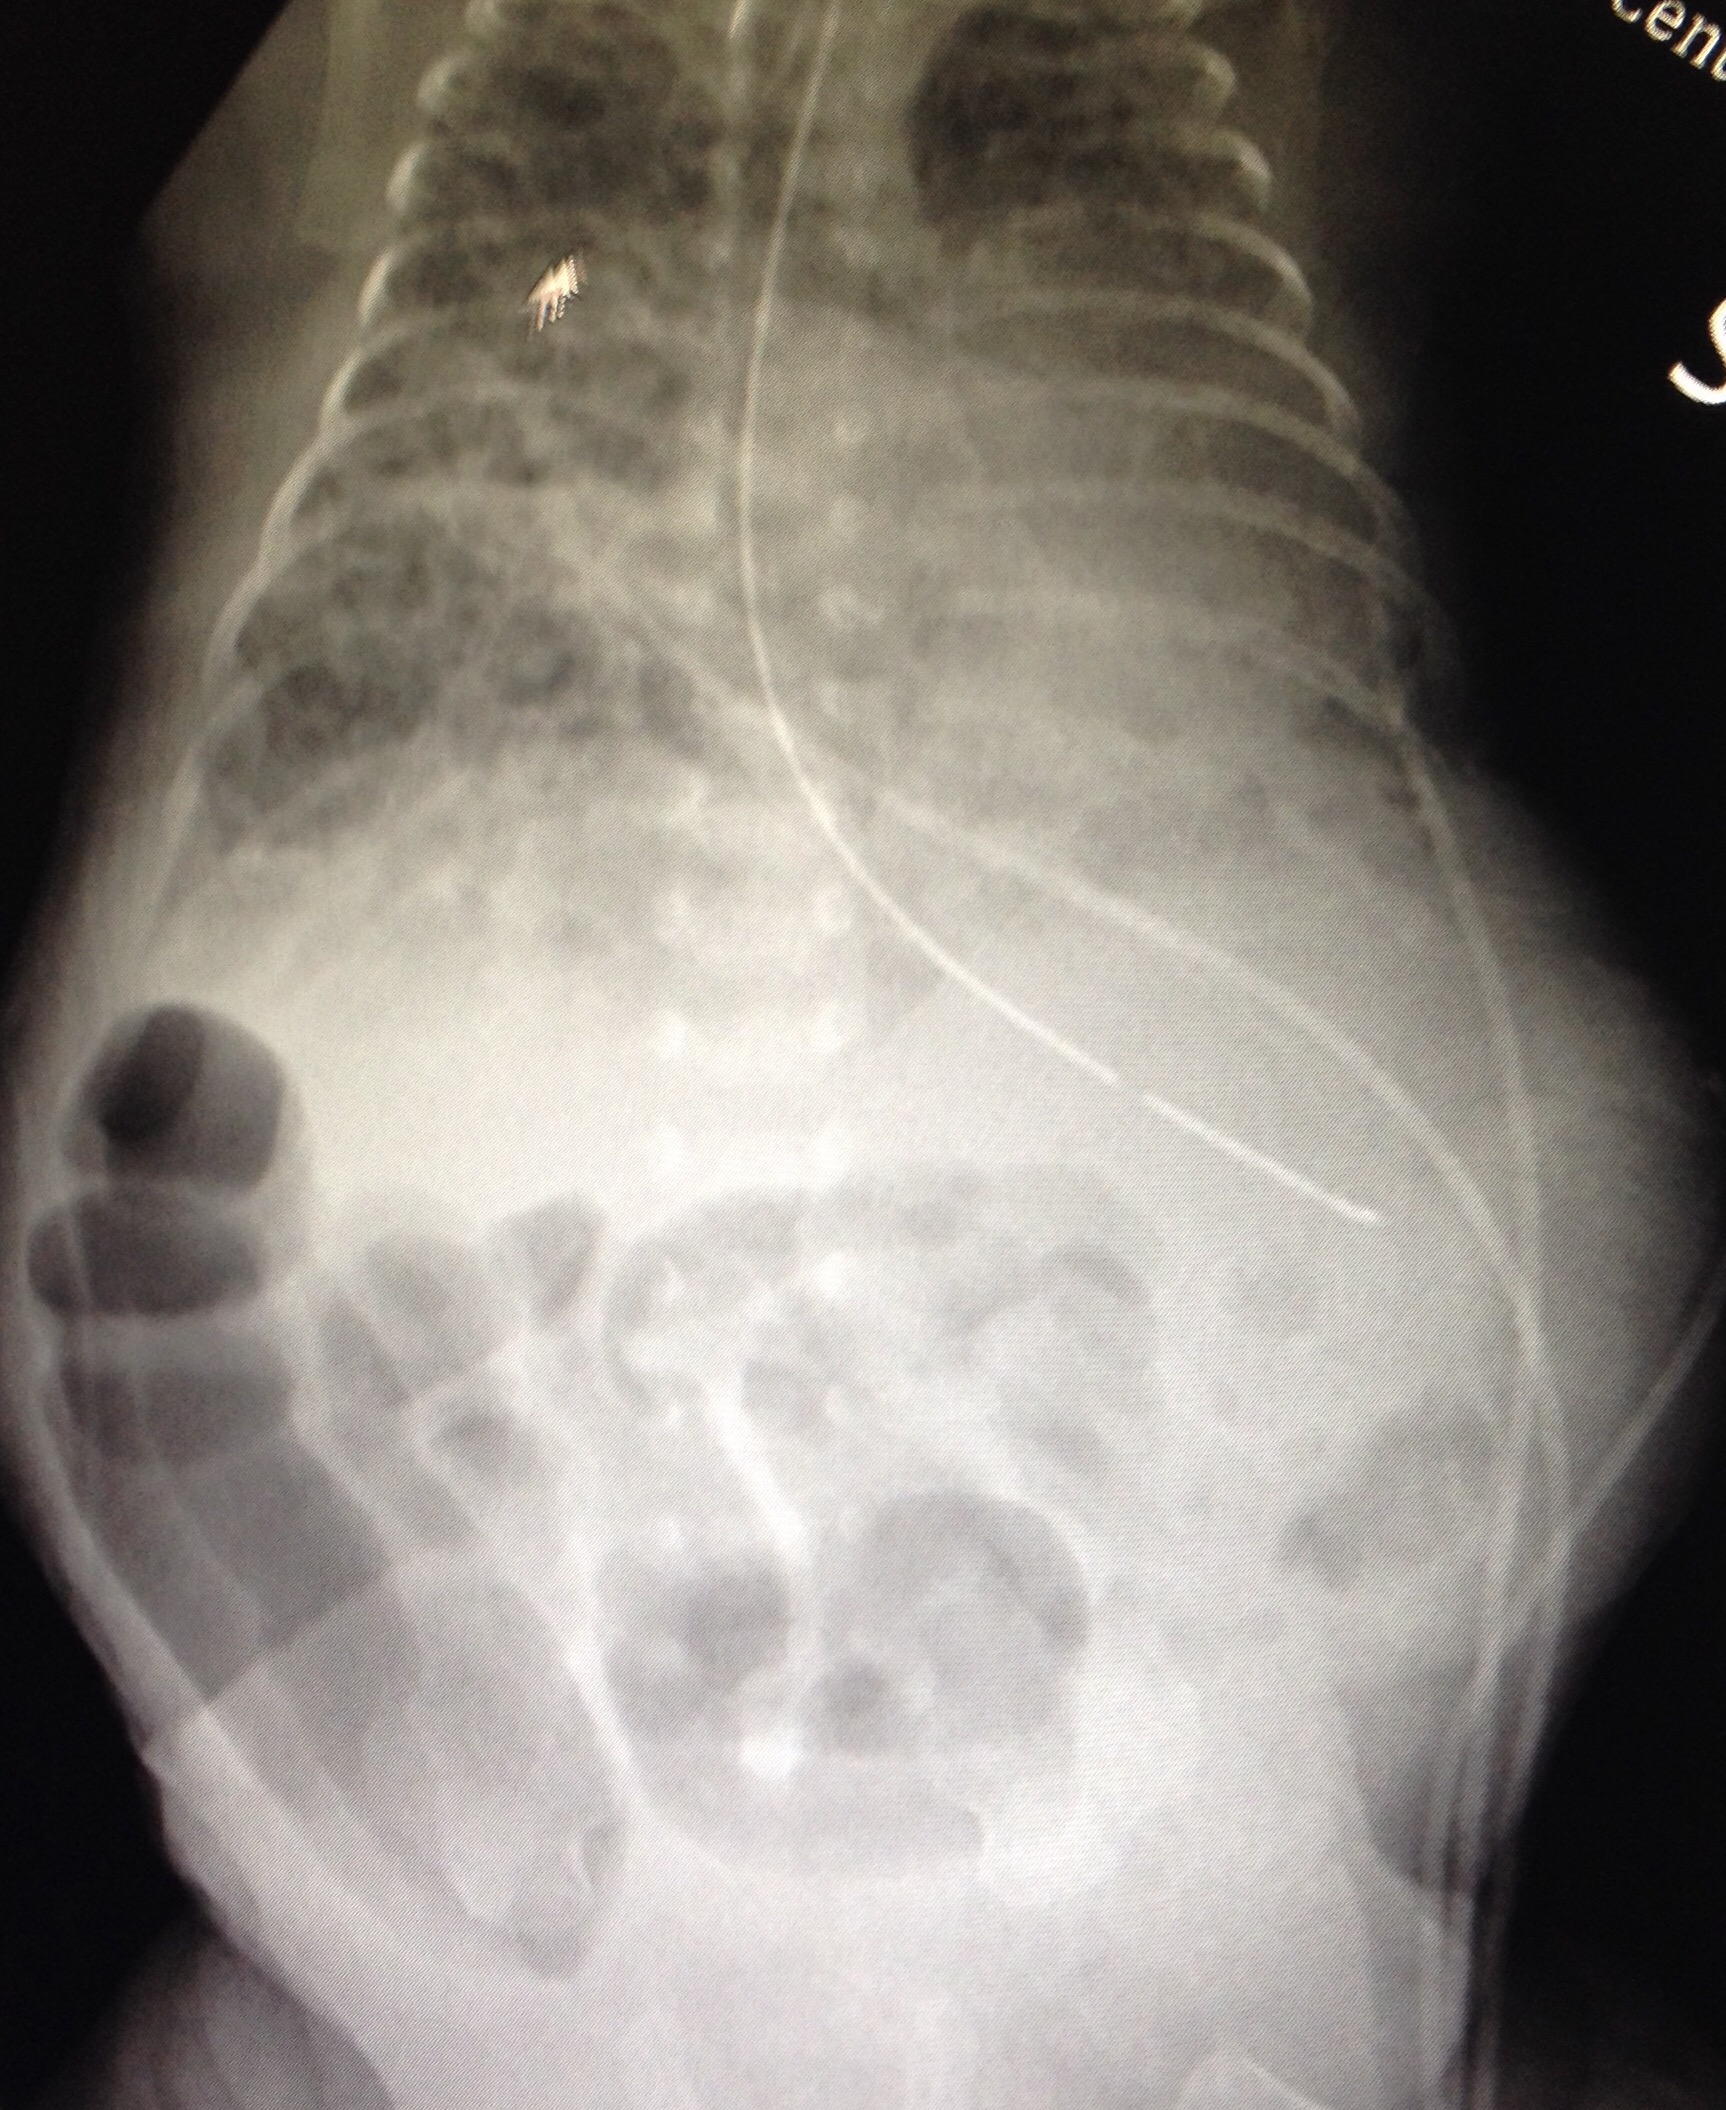

Then back to the NICU, RT is still hanging out at 34% oxygen!! Good job buddy!